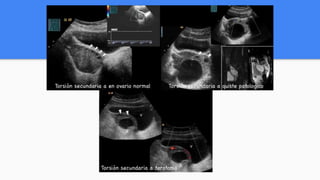

TORSIÓN DE OVARIO